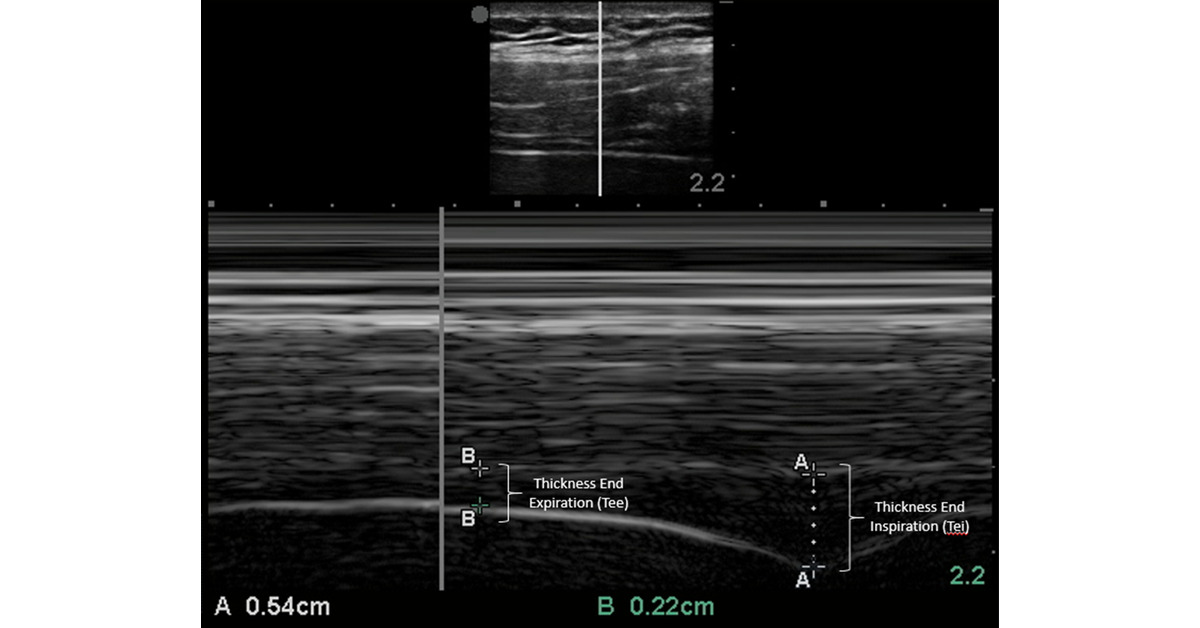

Finally getting to sit and listen to Dr. Beaubien’s #VExUS talk. I’m usually tied up with other workshop tasks when he or Eduardo Argaiz are presenting - feels good to share the stage today and actually enjoy the learning in peace. #KidneyWk